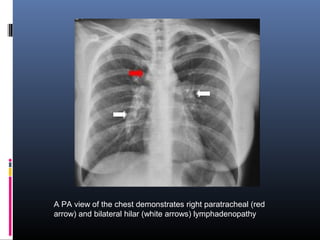

A PA view of the chest demonstrates right paratracheal (red

arrow) and bilateral hilar (white arrows) lymphadenopathy

A PA viewof the chest demonstrates right paratracheal (red arrow) and bilateral hilar (white arrows) lymphadenopathy

• #13 Stage I sarcoidosis. Posteroanterior chest radiograph demonstrates bilateral hilar and right paratracheal lymphadenopathy. Lung fields are clear.